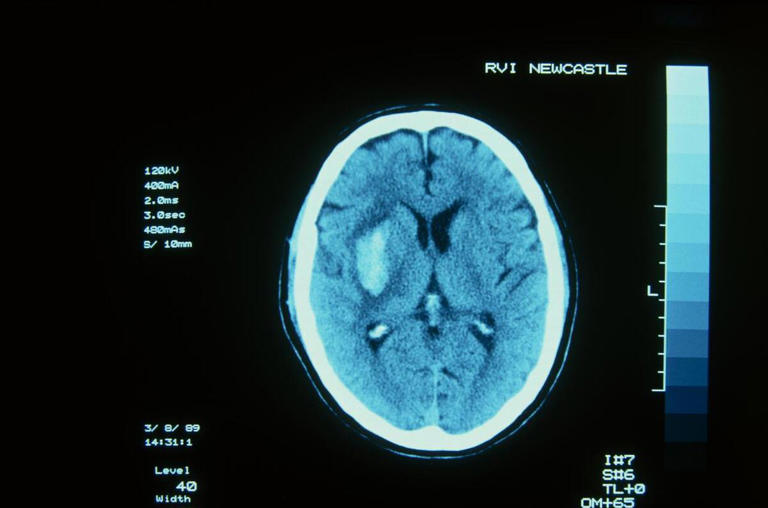

四是高血压脑出血。高血压的人容易发生脑出血,主要是因为高血压会引起脑内的小动脉硬化变形,让血管变得很脆,在激动的情况下,血压突然升高,超过硬化血管的承受能力,就像自来水管一样发生爆裂,这就是脑出血。

长期高血压还会让脑血管形成微动脉瘤,在血压出现波动时,也会造成脑出血的发生。